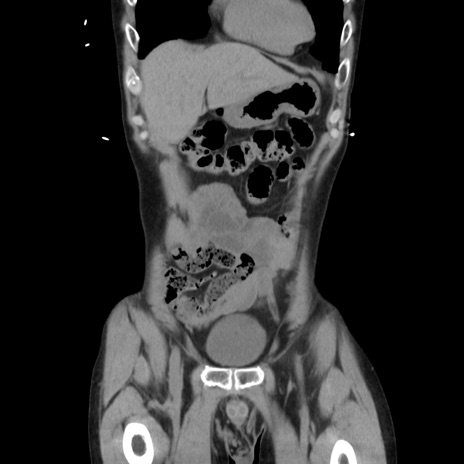

症例37(冠状断像)

【症例】40歳代 男性

【主訴】腹痛

【現病歴】4時間ほど前に電車に乗車中に臍部上より腹痛出現。徐々に増悪し起立困難となり、救急外来受診。生ものは数日食べていない。今朝お雑煮を食べた。

【既往歴】なし

【身体所見】BT 36.8℃、BP 117/84mmHg、HR 91/min、SpO2 97%、苦悶様、腹部:臍上部広範囲圧痛あり、反跳痛±

【データ】WBC 8100、CRP 0.03